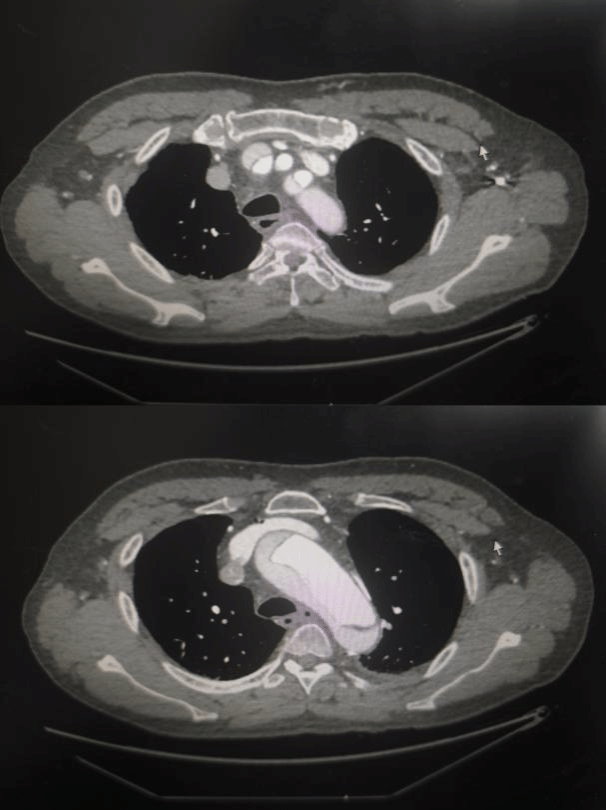

患者韩先生下午突发胸背部剧烈疼痛,呈撕裂样,当地医院处理后仍不能缓解,遂紧急送至西安交大二附院心血管病院。心内科张岩教授凭着丰富的临床经验,收入院后立即行急诊主动脉CTA检查,确诊为"Stanford A型主动脉夹层",血管内膜撕裂已延伸至升主动脉,随时可能破裂导致猝死。"这类患者48小时内死亡率超过50%,必须立即手术!"遂转入心血管外科。心血管病院副院长高峰教授迅速集结心外科团队,并紧急联系麻醉科、手术室、输血科等相关科室,在多学科联动下,成功启动"绿色生命通道"。凌晨12点紧急为患者进行了主动脉瓣成型+升主动脉置换+Sun’s手术。清晨7点,随着体外循环机缓缓停机,患者心脏重新有力跳动。术后转入心脏重症监护室,第二天即拔除气管插管,术后第四天转入普通病房。